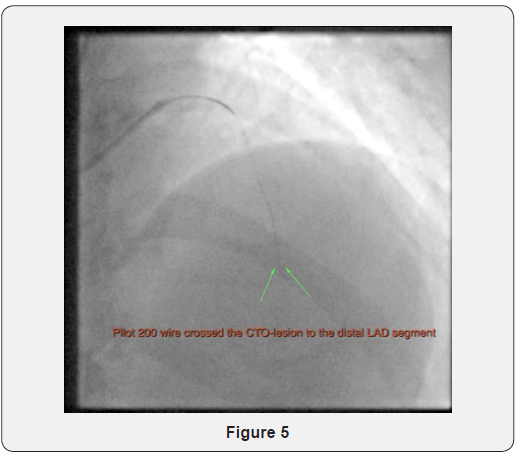

The Corsair was then advanced over the MB wire and been stuck within the lesion. The MB wire was then exchanged back to the Pilot 200 guide-wire which successfully crossed through the body of the CTO and the distal cap into the distal vessel (Figure 5 & 6).